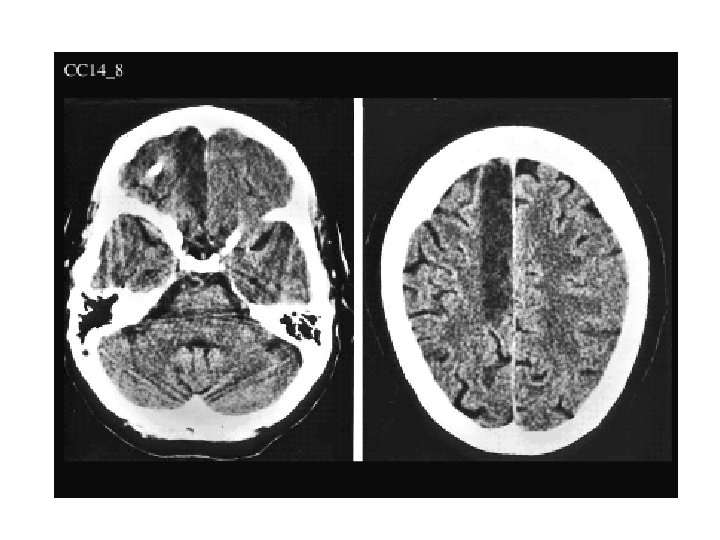

X 120 Anterior Comm ACA Fornix IIIrd Ventricle Thalamus & Pulvinar MCA Corpus Callosum Lateral Ventricle (Atrium) Optic Radiations Primary Visual Cortex Caudate Nuc (2 X) Internal Cap (AL, Genu, PL) Putamen Globus Pallidus (Ext & Int) External & Extreme Cap Claustrum Insular Cortex PCA